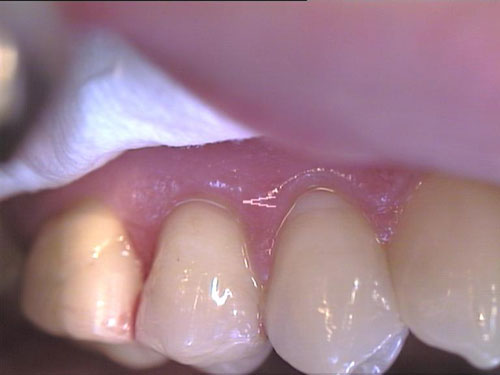

Zahnhalsempfindlichkeit